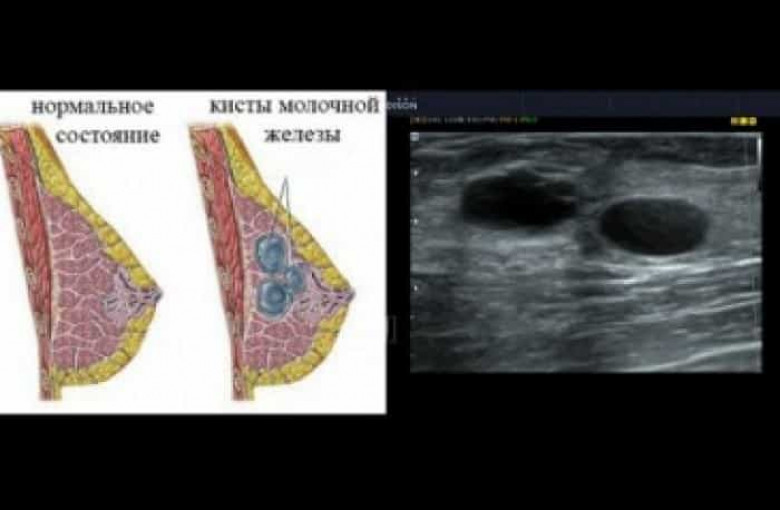

Ի՞նչ է կրծքագեղձի կիստան, և ինչպե՞ս բուժել այն

Կրծքագեղձի կիստան վերարտադրողական տարիքում գտնվող կանանց մոտ առաջացող բարորակ գոյացություն է, որն իրենից ներկայացնում է հեղուկով լցված պարկիկ: Կիստայի չափերը կարող են տարբեր լինել՝ մեկ միլիմետրից՝ մինչև մի քանի սանտիմետր:

Կիստան հազվադեպ է վերածվում չարորակ գոյացության, սակայն, եթե մաստոպատիա կամ հորմոնալ խանգարում կա, ապա կրծքագեղձի քաղցկեղի առաջացման ռիսկը մեծանում է: Կիստան, ինքնին, վտանգավոր չէ, սակայն դա չի նշանակում, որ այն բուժման կարիք չունի: